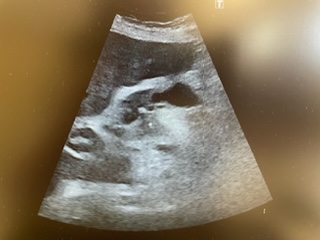

Descripción de los hallazgos ecográficos y las imágenes más relevantes para la resolución del caso

Realizamos POCUS en consulta y objetivamos líquido libre abdominal, así como hígado heterogéneo con distorsión grosera del parénquima, donde se objetivan dos lesiones hipoecogénicas de menos de 2 cm de longitud.